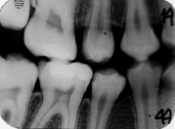

Leziunea posterioara apare ca o arie triunghiulara intunecata in smalt. Se poate afla pe suprafata externa a smaltului sau in profunzimea acestuia.

- leziune initiala de smalt situata pe fata distala a dintelui 4.5, vizibila ca arie triunghiulara intunecata in externa a smaltului pe radiografia bitewing.

In functie de gradul demineralizarii, leziunile vizibile pe radiografiile bitewing sunt codificate astfel:

0 - smalt sanatos, fara modificari vizibile radiologic;

1 - radiotransparenta limitata in smalt;

2 - radiotransparenta ce ajunge pana la jonctiunea smalt-dentina;

3 - radiotransparenta in smalt si externa a dentinei;

4 - radiotransparenta in smalt si interna a dentinei.